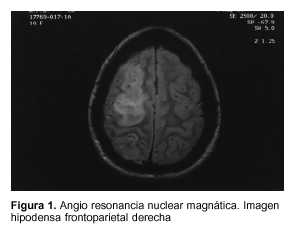

La tomografía computada de cráneo mostró una imagen hipodensa frontoparietal derecha, compatible con el diagnóstico de accidente cerebro-vascular de origen isquémico.

Se solicitó además angio resonancia nuclear magnética (figuras 1 y 2).

Al segundo día de evolución instala en forma aguda una monoplejia braquial izquierda, constatándose en la tomografía de cráneo una imagen hipodensa compatible con un infarto fronto-parietal derecho. Es de destacar que esta complicación surge cuando los parámetros de la coagulación se habían normalizado completamente.